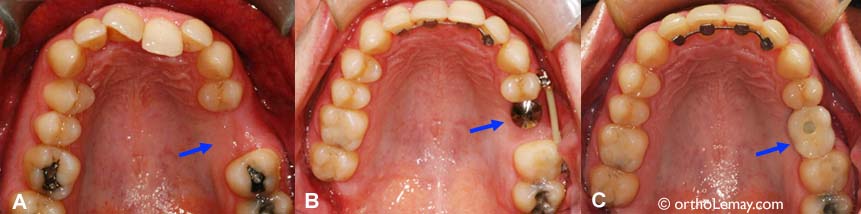

Remplacement de dents manquantes par implants dentaires 2

(A) Molaire supérieure gauche manquante chez un patient de 40 ans. (B) Après les corrections orthodontiques, un implant dentaire a été placé. (C) Après une période de guérison et stabilisation de 6 mois, une couronne a été fixée sur l’implant.